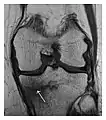

High-energy trauma fractures

Occult osseous injuries may result from a direct blow to the bone by compressive forces of adjacent bones against one another or by traction forces during an avulsion injury. Lesions in the tibial plateau, hip, ankle, and wrist are often missed. In a tibial plateau fracture, any disruption of the posterior and anterior cortical rims of the plateau should be sought. Impaction of subchondral bone will appear as an increased sclerosis of the subchondral bone (Figure 1). In the hip, posterior acetabular fractures also present subtle radiographic findings. The acetabular lines should then be carefully examined keeping in mind that the posterior rim, which is harder to see on X-rays, is more frequently fractured than the anterior rim (Figure 2). In the wrist, detection of carpal bone fractures is often challenging, with up to 18% of scaphoid fractures radiographically occult. Carpal fractures, especially the scaphoid, are associated with the risk of avascular necrosis. In apparently normal wrist radiographs from symptomatic patients, if there is history of a fall on an outstretched hand with pain in the anatomic snuffbox, suggesting scaphoid injury, the initial examination with posteroanterior, lateral, and pronation oblique views must be complemented by other specific views such as supination oblique and the "scaphoid" view A careful examination of cortices for evidence of discontinuity or offset and cancellous bone for lucency is necessary (Figure 3).[1]

a

b

c

Figure 1: A 56-year-old woman presenting with left knee pain after a fall. (a) Initial anteroposterior radiograph was considered normal, however, subtle cortical disruption of the anterior rim of the medial tibial plateau, medial to the tibial spine, is noted (arrow). (b) Coronal T1-weighted MRI confirms the cortical disruption (arrow) and shows extensive fracture through the proximal tibia. (c) Coronal proton density-weighted image with fat saturation shows extensive edema in the subchondral bone. Note also hypersignal adjacent to the medial collateral ligament corresponding to a grade I sprain (arrowheads).[1]